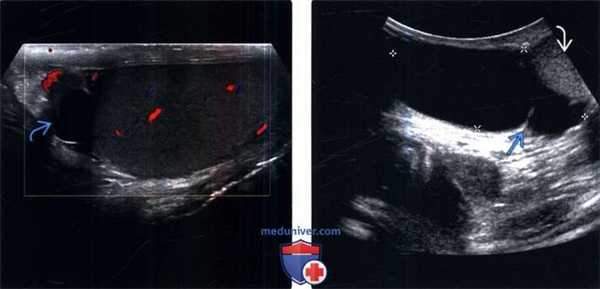

(Слева) УЗИ: обычная картина случайно обнаруженной и клинически не значимой кисты придатка. Обратите внимание на анэхогенное аваскулярное образование с четкими контурами в головке придатка.

(Справа) УЗИ, визуализируется крупная киста придатка (метки) с одиночной тонкой перегородкой в правой половине мошонки, смещающая яичко В книзу. Обратите внимание на то, что для обнаружения такого крупного образования потребовался абдоминальный датчик, а не высокочастотный линейный.